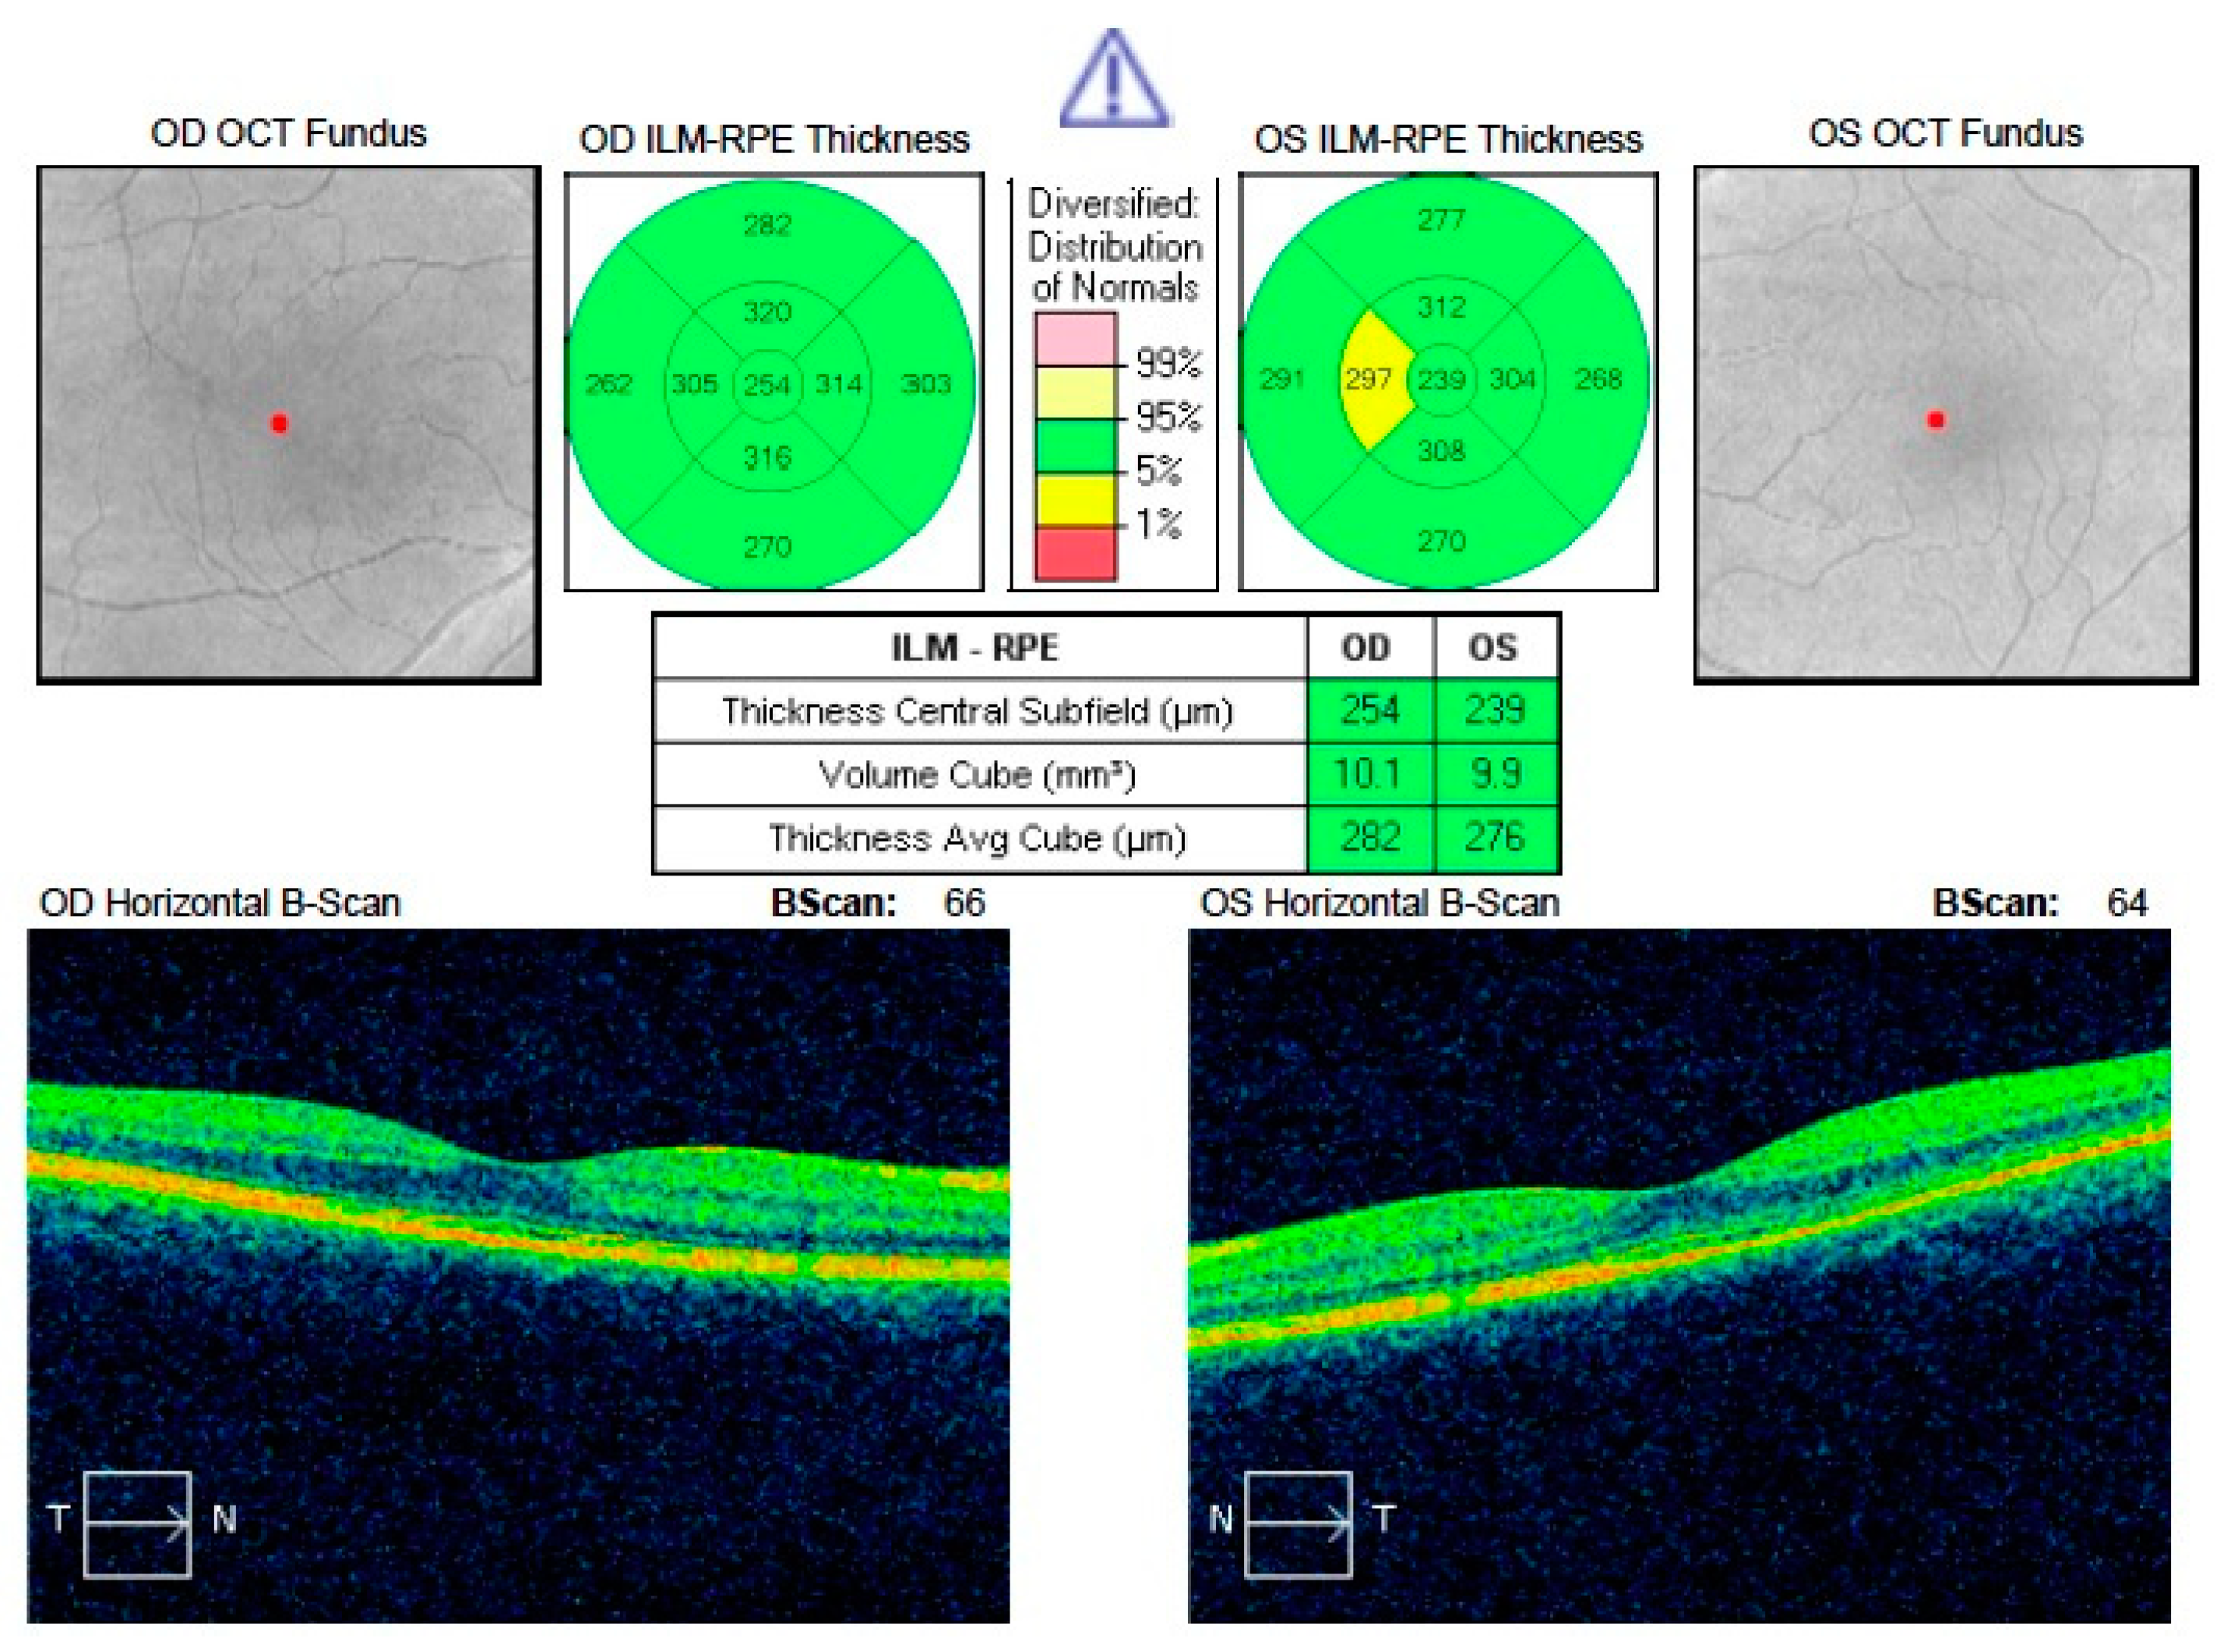

| CRT (µm) | 406.40 | 403.00 | 96.62 | 238.80 | 240.00 | 23.39 | <0.0001 |

| CRT (µm) | 238.80 | 240.00 | 23.39 | 264.87 | 266.00 | 21.22 | 0.000023 |

| MFT (µm) | 178.93 | 174.00 | 16.88 | 199.47 | 194.00 | 17.87 | 0.001 |

| BCVA (logMAR) | 0.11 | 0.10 | 0.13 | 0.01 | 0.00 | 0.04 | 0.01 |